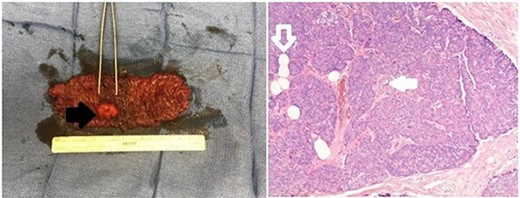

Endoscopic ultrasound (EUS) revealed a 1-cm submucosal antral mass. Due to size and wall involvement, pancreatic rest was suspected, though the jejunal lesion multifocal carcinoid tumor remained in the differential. An endoscopic mucosal resection of gastric lesion was performed, but pathology again was inconclusive. As the jejunal mass was noted to be 20–30 cm distal to the ligament of Treitz, and a miniprobe EUS was utilized to access this location. The small bowel lesion was hypoechoic, well demarcated, 2 cm and arose from the muscularis propria. Due to the size, location and depth of wall involvement, an endoscopic biopsy or resection was not feasible and formal surgical resection was recommended. Therefore, a robotic small bowel resection was performed. The previously marked jejunum was identified adjacent to a large mass with associated enlarged mesenteric lymph nodes (Fig. 1). Approximately, 13 cm of jejunum and mesentery were resected (Fig. 2). Pathologic examination revealed a 2.6-cm submucosal mass with pancreatic features, including acini, ducts and Islet cells, confirming pancreatic rest (Fig. 2).

Gross and pathologic representation of resected pancreatic rest; the resected portion of jejunum was opened to reveal an intraluminal mass (solid black arrow); the mass underwent further pathologic evaluation, which revealed acini, ducts (outlined white arrow) and Islet cells (solid white arrow) specific to the pancreas and confirming the diagnosis of pancreatic rest.